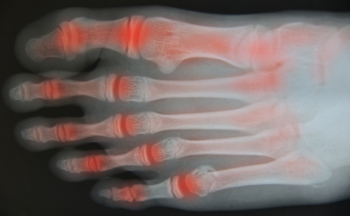

Is Rheumatoid Arthritis Common?

One of the most common types of arthritis is referred to as rheumatoid arthritis. Many people may experience symptoms of this condition in the feet and are aware of the pain and discomfort that typically exists with this ailment. There are specific symptoms that may accompany this type of arthritis, including swelling and soreness in the feet, difficulty waking, which may be a result of unstable joints, or the foot possibly changing shape. Research has shown the part of the foot that may be affected the most are the toes, which consist of smaller joints. They may begin to look deformed and may have difficulty in moving or bending. There may be additional foot conditions that may arise including the development of corns and calluses. This may be a result of changes in the foot shape. If you are afflicted with rheumatoid arthritis, it is suggested to consult with a podiatrist who can offer proper treatment techniques.

Rheumatoid Arthritis (RA) is an autoimmune disorder in which the body’s own immune system attacks the membranes surrounding the joints. Inflammation of the lining and eventually the destruction of the joint’s cartilage and bone occur, causing severe pain and immobility.

Rheumatoid Arthritis of the Feet

Although RA usually attacks multiple bones and joints throughout the entire body, almost 90 percent of cases result in pain in the foot or ankle area.

• Swelling and pain in the feet

• Stiffness in the feet

• Pain on the ball or sole of feet

• Joint shift and deformation

Quick diagnosis of RA in the feet is important so that the podiatrist can treat the area effectively. Your doctor will ask you about your medical history, occupation, and lifestyle to determine the origin of the condition. Rheumatoid Factor tests help to determine if someone is affected by the disease.